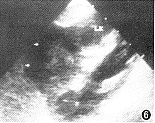

图6 与图4同一病例。B超显示肾实质内孤立的中等强度回声结节

11例白血病肾浸润患儿中,9例为双肾浸润,其中双肾弥漫浸润4例,双肾多发结节浸润5例,9例中ALL 8例,ANLL 1例。CT平扫见弥漫浸润为两肾轮廓增大,肾包膜完整光滑,肾实质明显增厚,肾实质密度无异常,肾窦形态基本正常,增强后肾盂、肾盏显影轻度延迟。B超显示肾影增大、肾实质增厚的同时还显示回声均匀增强。 多发结节浸润的平扫CT见肾实质内多发的略高密度结节影,结节间可见线状低密度影将其分开(图1),结节突起使肾表面呈轻度分叶状。增强后肾实质内结节呈轻微强化,较平扫增长18 HU,密度均匀,结节内无低密度坏死区或出血,结节间见强化后受结节挤压变形的肾实质与集合系统,呈高密度分支状影(图2),肾实质强化程度较正常减低,在结节间自肾被膜下延伸至肾窦,肾盏变形拉长,肾盂显影明显延迟。B超显示肾实质回声增强,内见多发大小不等的结节(图3),中等强度回声,肾结构不清。化疗后复查,CT平扫显示双肾大小、形态基本恢复正常。本组2例呈单发结节浸润,均为ANLL。平扫CT见肾实质局限增厚,表面隆起,密度较正常肾实质略高,境界模糊(图4),增强后见肾实质内单发结节状影轻微强化,较平扫增长22HU,结节与正常肾实质间界限清楚(图5),肾被膜完整。B超显示肾实质内孤立中等强度回声结节(图6),肾结构受挤压变形。化疗后复查B超显示肾形态基本恢复正常。 本组化疗后5例复查CT与B超,显示肾轮廓明显缩小,肾实质厚度、密度或回声接近正常。11例患儿肝、脾均有不同程度增大。8例ALL患儿CT或B超检查同时显示胸腺浸润1例;肺及胸膜浸润4例;肾上腺浸润2例;腹膜后淋巴结浸润1例。3例ANLL患儿除肝、脾增大外CT或B超检查未显示其他脏器浸润。